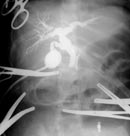

Таким образом, дооперационная диагностика кистозной трансформации желчевыводящих путей в настоящее время значительно улучшилась благодаря применению современных методов исследования. Однако, выбор оперативного метода лечения окончательно может быть произведен только во время операции, так как решающее значение в верификации диагноза имеют интраоперационные рентгеноконтрастные методы исследования, которые позволяют выявить кистозные расширения вне- и внутрипеченочных желчных протоков, степень и протяженность их дилятации, проходимость терминального отдела холедоха, рубцовые сужения печеночных протоков, билиопанкреатический рефлюкс. Поэтому всем больным после лапаротомии производилась интраоперационная холангиография и, на основании полученных данных решался вопрос о выборе метода хирургического лечения. Данная методика выполнена 10 пациентам (Рис. 3).

Рис. 3. Интраоперационная холангиография.